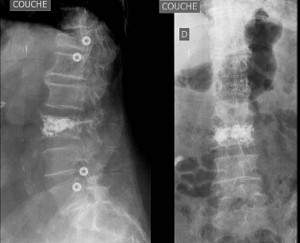

Tassements vertébraux - Fractures en compression

Fractures thoraciques et lombaires